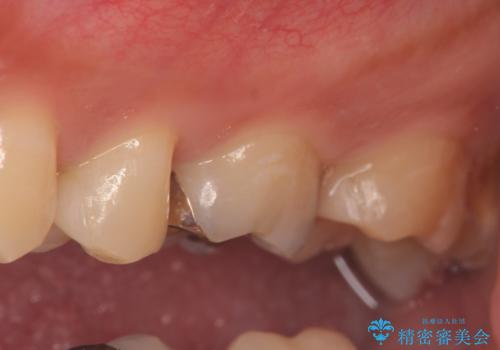

左上5、6、7番目の歯に虫歯を認めたため、左上5、7はセラミックインレーによる修復を行いました。

当院のセラミックインレーはemaxという強度と審美性に優れた材料を使用しています。

またプレス方式でインレーを製作しているため、削り出しで製作するCADCAMより優れた適合性も持ち合わせており、虫歯が再発しにくい修復物です。